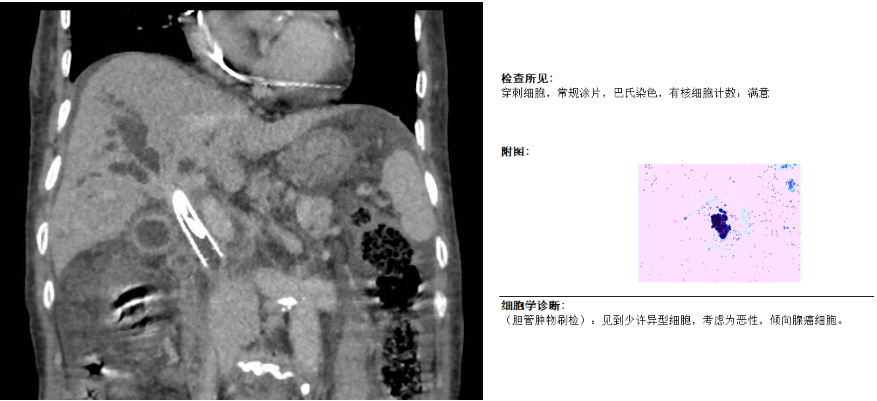

孙志强反复阅片后分析该患病情:梗阻部位处于肝总管、胆囊管交汇处,属高位胆管梗阻,不宜行内镜下逆行胆管引流术(ERCP),可行经皮肝穿刺胆管引流术(PTCD),再根据胆管造影情况来判断能否行胆道支架置入术。在明确患者没有手术禁忌症后,于CT导引下行PTCD,后于DSA导引下行胆管造影。因胆管梗阻严重,造影后无法通过,即便利用导丝导引也十分困难。经过反复尝试和更换不同硬度导丝后,终于导丝越过梗阻部位,导丝导引导管成功完成胆道造影,明确了梗阻的部位和长度,最终顺利完成了本次胆道支架置入手术。

术后第2天,患者皮肤、巩膜黄染缓解,尿色变浅。1周后患者胆汁引流量明显减少,总胆红素降至98 umol/L。再次分析病情后,复查胆道造影见造影剂顺利通过狭窄部位并进入十二指肠,证实胆道通畅,拔除胆道引流管。同时术中利用胆道活检毛刷进行刷检,成功刷取胆道病变组织一块,送病理回报:考虑恶性,倾向腺癌。最终明确诊断为:胆管癌,为接下来的抗肿瘤治疗提供了可靠的证据。